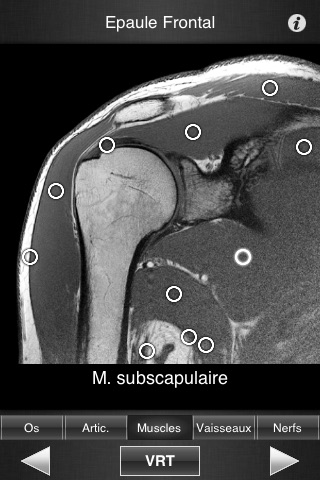

Il contient 502 coupes d’IRM jointives (2-4 mm dépaisseur) dans les trois plans de l’espace.

- Plus de 500 légendes différentes, fidèles à Terminologia Anatomica et à la littérature récente.

- Plus de 16 000 repères anatomiques définis.

- Lecture des légendes facilitée grâce à une segmentation en cinq modes (os, articulation, muscles, vaisseaux, nerfs)

- Images de haute qualité avec fonction de zoom